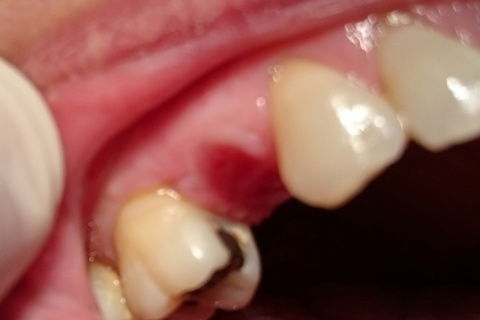

Foto incial.

Paciente sexo feminino,aproximadamente 40 anos, encaminhada pelo protesista para exodontia do elemento 14 e implantação. O mesmo verificou trinca na raíz do elemento 14. Após documentação e paciente avaliado o tratamento de opção em comum acordo com a paciente foi , exodontia, implante imediato com ROG (alobone) e enxerto gengival livre para ocluir o alvéolo, com provisório tipo aleta e função tardia. (Caso em andamento).